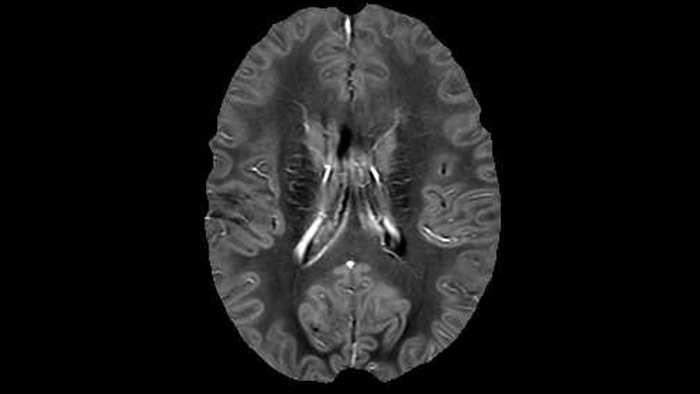

“In addition to traditional imaging like FLAIR for lesion identification, we see a real push towards techniques that weren’t normally required for MS, including good highresolution 3D T1 weighted images to do volumetrics. We’ve also started looking at spinal cord imaging again, since techniques have improved in terms of acquisition and analysis. Another important technique is susceptibility weighted imaging (SWI), particularly if we are looking for central veins in lesions, which is extremely helpful for diagnosis.”

of limiting MWI to the brain, even without the cerebellum, we can now spend about the same amount of time and scan the whole brain and the cervical spinal cord, which is a huge boost for us.” Dr. Rauscher says, “For MWI we perform 3D T2 with 32 or more echoes. This used to take a long time, but with Compressed SENSE we can decrease this to ten minutes for the whole head. Because of the large field of view (FOV) on the readout direction, we even get information from the brainstem, which we previously missed when we were using the GRASE approach. Having the whole head scan is nice because it has spatial resolution, orientation and FOV that are comparable to the standard 3D clinical MS scans, including the FLAIR and 3D T2, and a 3D T1 for brain volume.”

T1 - Weighted, Myelin Water Fraction Superimposed

Spinal cord coverage

Smaller, more isotropic voxels

Excellent detail in quantitative maps

Images courtesy of Adam Dvorak, Department of Physics and Astronomy, University of British Columbia

He says the accelerated scanning is achieved via the use of Compressed SENSE and MultiBand SENSE. “We can use Compressed SENSE acceleration factors of about 10 on a 3D FLAIR for instance, which is quite remarkable compared with what we saw with the Achieva. With 3D FLAIR, we can push the spatial resolution to 0.3 cubic mm and it works. Previously, our 3D FLAIR scans lasted about 8 minutes, but now with Elition they are five minutes. The SNR is also visibly better. Our SWI and QSM scans look fantastic. Also, since a lot of neuroimaging is EPI based, using the MultiBand SENSE technique can increase temporal resolution and make it possible to run complicated DTI scans relatively quickly.”

Sagittal 3D FLAIR with 0.3 mm3 voxel volume acquired in 5:12 min. using Compressed SENSE showing a (juxta)cortical MS lesion.

QSM based on a Compressed SENSE multi-echo SWI.